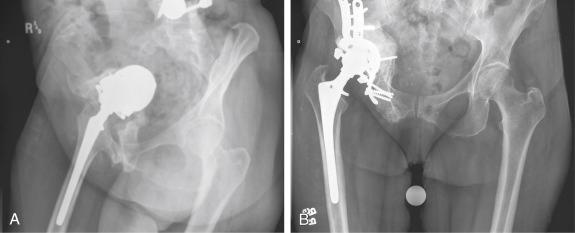

A 54-year-old male had a failed attempt of an acetabular reconstruction with a bilobed component ( Fig.55.1 ). He was found to have a large posterior column defect and a pelvic dissociation. A cage reconstruction with bone grafting was used to bridge the discontinuity.

FIGURE 55.1, A, A 54-year-old patient underwent repeat surgery immediately after a failed attempt at implantation of a bilobed acetabular component. B, The patient had a pelvic discontinuity in addition to the medial wall defect.